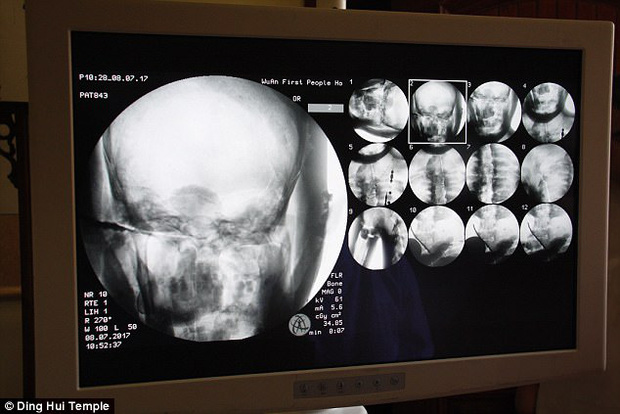

Theo tờ Daily Mail, đầu tháng 7 năm 2017, các nhà khoa đã tiến hành chụp CT để "nhìn thấu" bên trong xác ướp mạ vàng của nhà sư Ci Xian nổi tiếng Trung Quốc. Nhà sư Ci Xian được cho là một nhà sư được vạn dân kính trọng, ông đã đi từ Ấn Độ cổ đại đến Trung Quốc cổ đại để quảng bá Phật giáo.

Ngày 8/7/2017, trước sự chứng kiến của các nhà sư, giới truyền thông và nhiều người dân, các nhà khoa học đã tiến hành chụp CT xác ướp nhà sư Ci Xian.

Ban quản lý của ngôi chùa đã sắp xếp một buổi chụp CT xác ướp nhà sư Ci Xian vào ngày 8 tháng 7 năm 2017.

Mọi người đều bàng hoàng khi các bác sĩ cho biết nhà sư Ci Xian vẫn còn nguyên bộ xương, và một bộ não hoàn chỉnh. Tức xác ướp này đã được bảo quản gần như nguyên vẹn sau hơn 1.000 năm. Điều này khiến giới khoa học sửng sốt với kỹ thuật ướp xác thời bấy giờ.

Bác sĩ Wu Yongqing nói với kênh Pear Video sau khi tiến hành chụp CT cho xác ướp: "Chúng tôi có thể thấy xương của ngài ấy khỏe mạnh như một người bình thường. Hàm trên, răng trên, xương sườn, xương sống và tất cả các khớp đều vẫn nguyên vẹn. Thật không thể tin được khi thấy điều này".